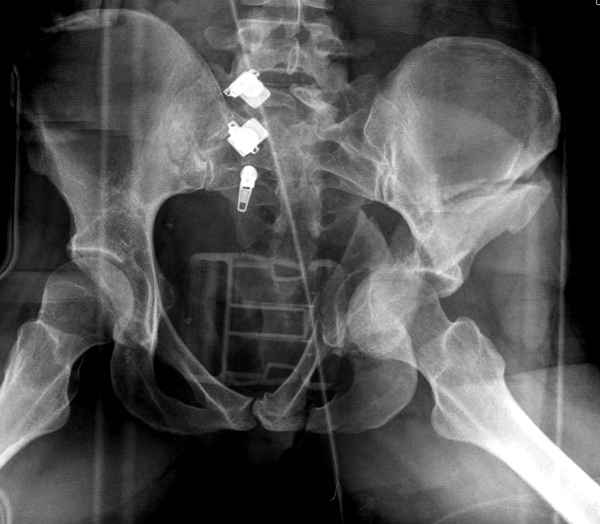

Интересно было бы посмотреть рентгенограммы до операции. У меня впечатление, что я не все вижу, что тут есть... Уважаемые Господа "тазисты" и "тазологи", к какому типу переломов вертлужной впадины по Летурнелю вы бы отнесли это случай?

Из переломов проходящих через крыло и/или заднюю стенку ни простой перелом "передней колонны" (явно имеется пером задней стенки, и не видно перелома седалищной или лонной), ни простой "поперечный", ни ассоциированный "Т-образный" (т.к есть перелом крыла и не видно перелома седалишной), ни ассоциированный "задняя колонна+задняя стенка", на ассоциированный "поперечный+задняя стенка", ни ассоциированный "передняя колонна+задняя гемисфера" (не видно перелома седалищной), ни ассоциированный "обе колонны" (не видно перелома лонной седалищной) не подходят под эту классификацию....

>Вопрос к знатокам: Так что это?

к таковым себя не причисляю, но...обычное дело для нашей страны - выкладывать 3D и не показывать стандартные проекции Judet. Дигност представляет те ракурсы, которые по-его мнению наиболее информативны, более того комп сам достраивает какие-то мелкие повреждения по 3D по своему усмотрению. По данной реконструкции можно предполагать высокий двухколонный перелом с оскольчатыми передней и задней колоннами, оскольчатую высокую переднюю колонну с задним полупоперечником или одно из перечисленных с вовлечение КПС. У меня впечатление за второй вариант, но нужно обследовать нормально - проекции, сканы.

высылаю дополнительно сканы.

итак, второй вариант: высокий двухколонный с вовлечением КПС... Ни одно из основных повреждений не репонировано, кроме задней стенки. Скорее всего попытка реконструкции вертлуги сейчас будет очень травматичной и не очень эфективной, т.е. вероятный риск более значим, чем ожидаемая польза... Лучше подождать, и потом сразу эндопротез

Когда перелом не получается отнести к какому либо типу - эффективнее всего описать более детально. В дальнейшем проще бывает сортировать, и что важнее - "руководство к действию" бывает более обоснованным. В данном случае графа клинического диагноза может выглядеть так: Застарелый разрыв правого крестцово-подвздошного сочленения, консолидирующиеся со смещением переломы крыла и тела правой подвздошной кости, обеих колонн и задней гемисферы правой вертлужной впадины. Состояние после остеосинтеза.

мы имеем дело с полупоперечным переломом у которого отломался задний край или его отломали, превратив перелом в полный двухколонный.

По отдельным срезам и тем более по реконструкции трудно судить о сращении крыла и задней колонны с осевым скелетом.

В большинстве случаев при двухколонных переломах

в итоге получается прочный бублик с дыркой. При эндопротезировании в дырку помещается головка, а чашка должна неплохо заклиниться в бублике.

Главное, чтобы бублик не был разорван, что не очень понятно на представленных снимках.

Все выступающие коллеги высказались насчет необходимости стандартных снимков по Judet, потому что для определения тактики лечения переломов вертлужной впадины 3Д снимки малоинформативны.

Из того минимума, что представлено, мне кажется, мы имеем дело с двухколонным переломом вертлужной впадины. Обычно медиальный (центральный) "вывих" головки встречаются в сложных двухколонных переломах со смещением.